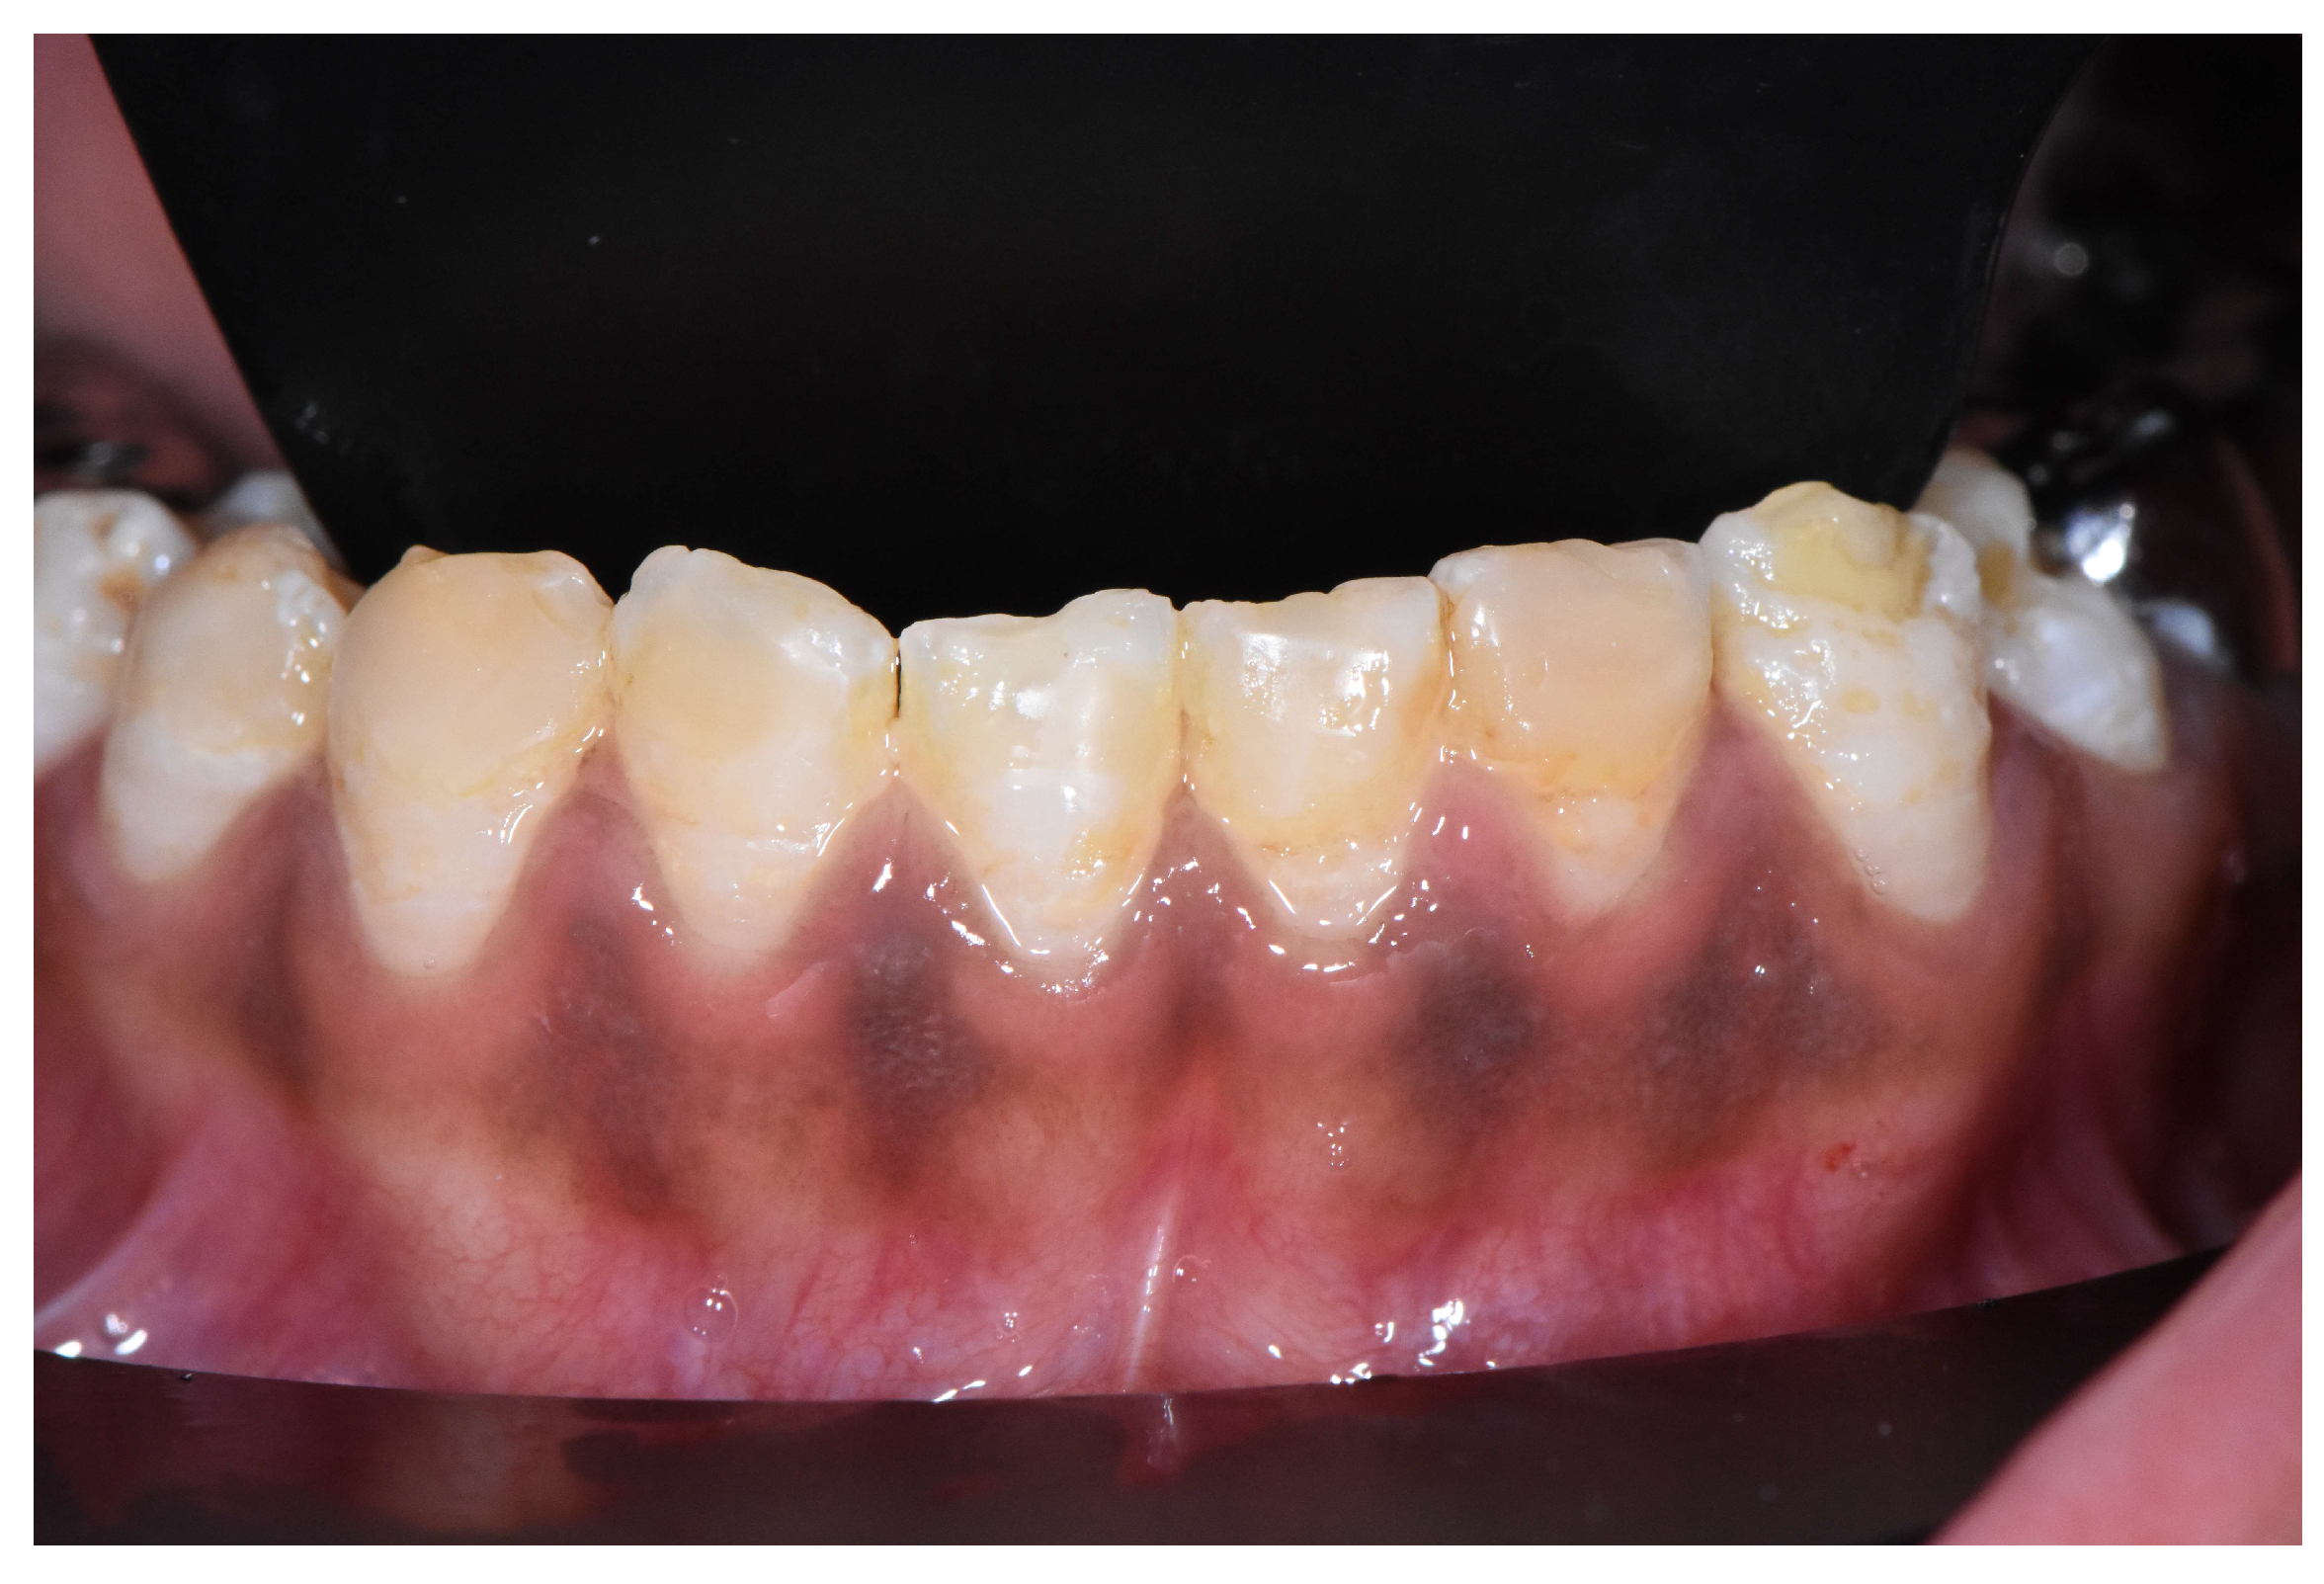

2.2. Clinical Examination

2.3. Radiographic Examinations